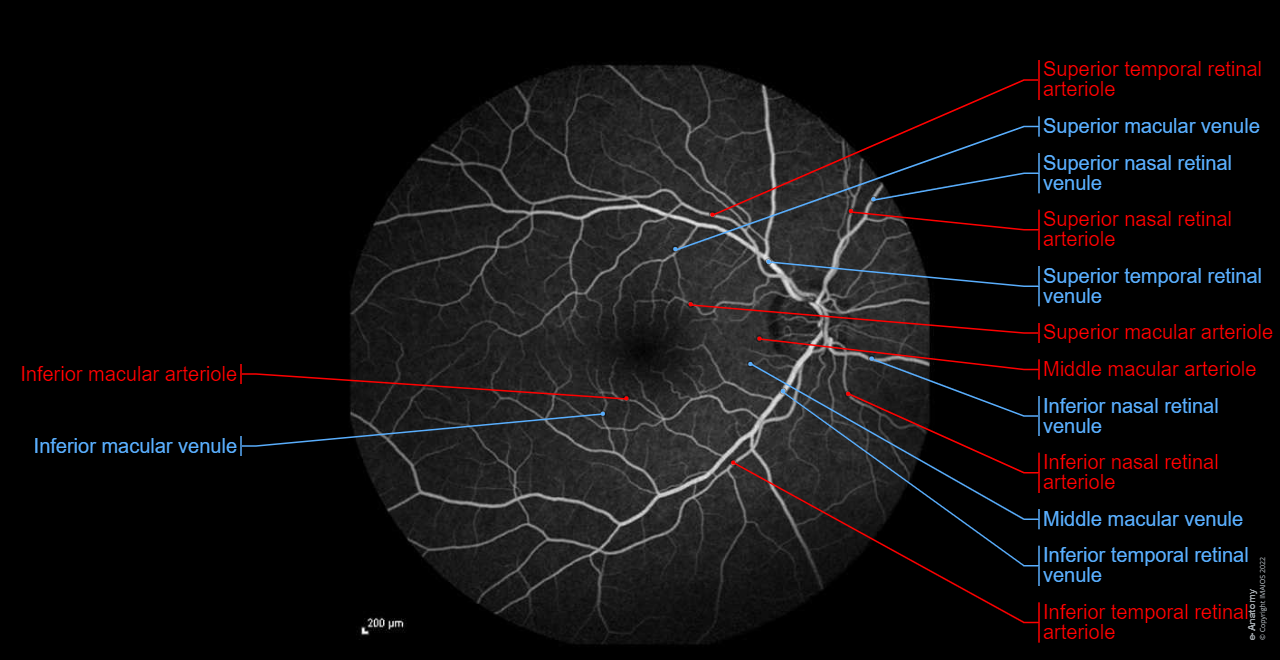

Fluorescein angiography: Central retinal artery, Central retinal vein

Fluorescein angiography